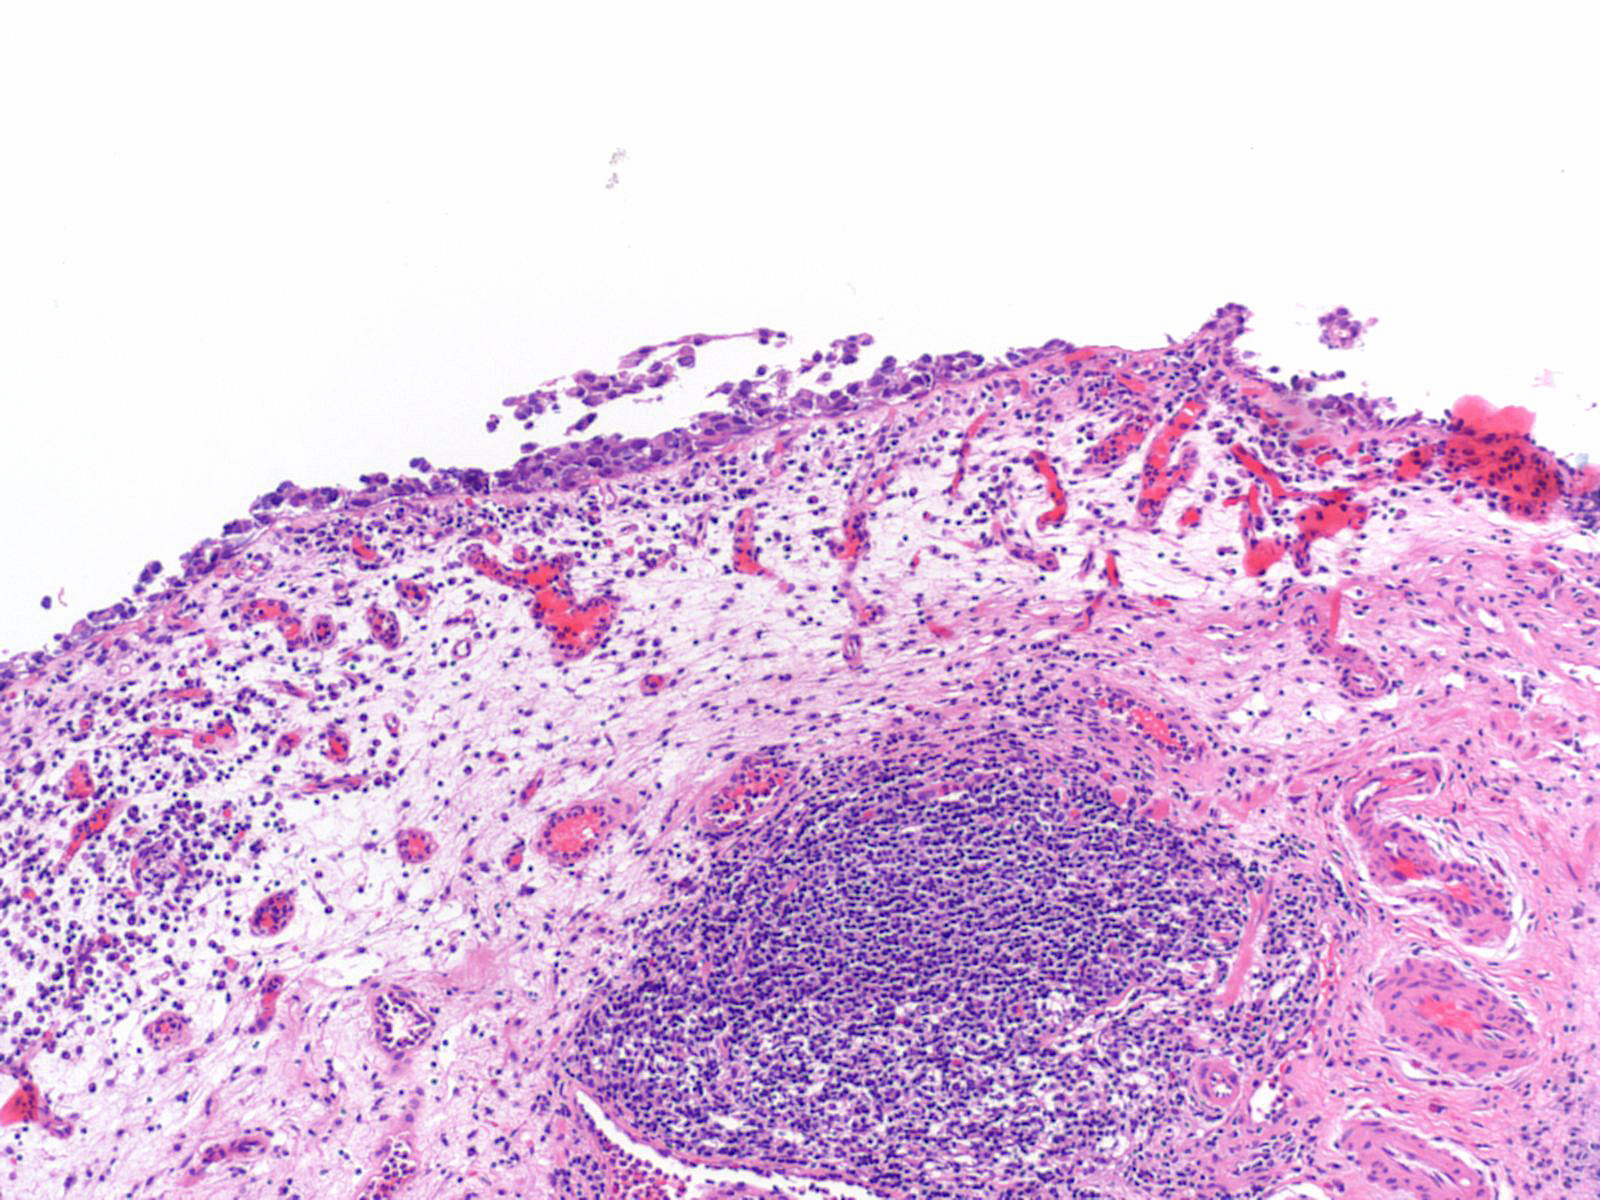

Consensus grade: Carcinoma in situ (CIS)

Lesion shows marked variation in nuclear size, shape and chromatin. Architecturally, cells appear irregularly clustered and the epithelium is disorganized.